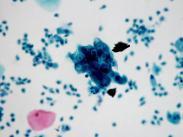

呈孤立的圓形肺炎變的肺炎謂球形肺炎(spherical pneumonia),是一個以X線胸片的形態表現特點而命名的肺炎。

球形肺炎,球形肺炎癥狀,球形肺炎治療